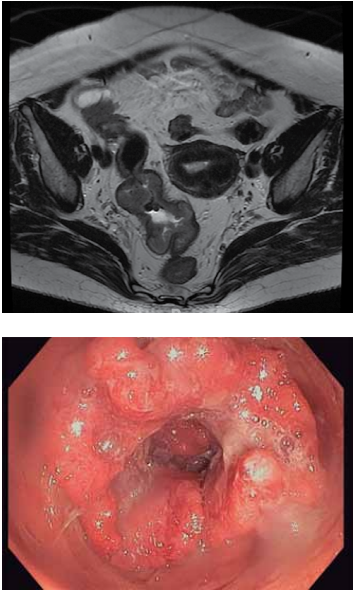

Mulher, 70 anos, DM tipo 2 e HAS, ambas com controle adequado. Hematoquezia há 3 meses. Refere emagrecimento não intencional de 10 kg, em 6 meses. Exames laboratoriais: Hb 10,9 g/dL, plaquetas 220 mil/uL,

Cr 0,95mg/dL, INR 1,0, R 0,95, PCR 15,2 mg/dL, ferritina 40 ng/mL, saturação de transferrina 12%, albumina

3,5 g/dL. Exames de estadiamento negativo para metástases. Realizados os exames diagnósticos a seguir.

Qual é o diagnóstico e como deve ser feita a condução dessa paciente no pré-operatório?